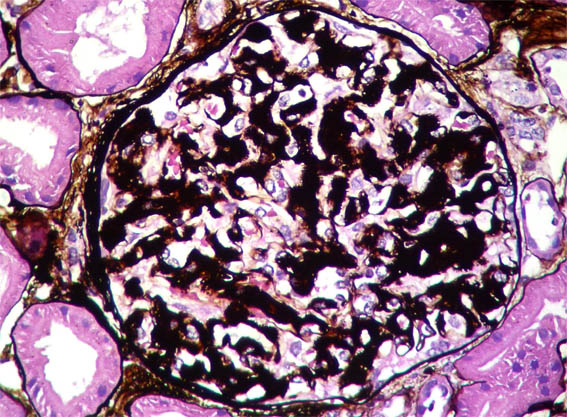

Figure 6. Methenamine-silver stain, X400.

Figure 7.

Methenamine-silver stain, X400.